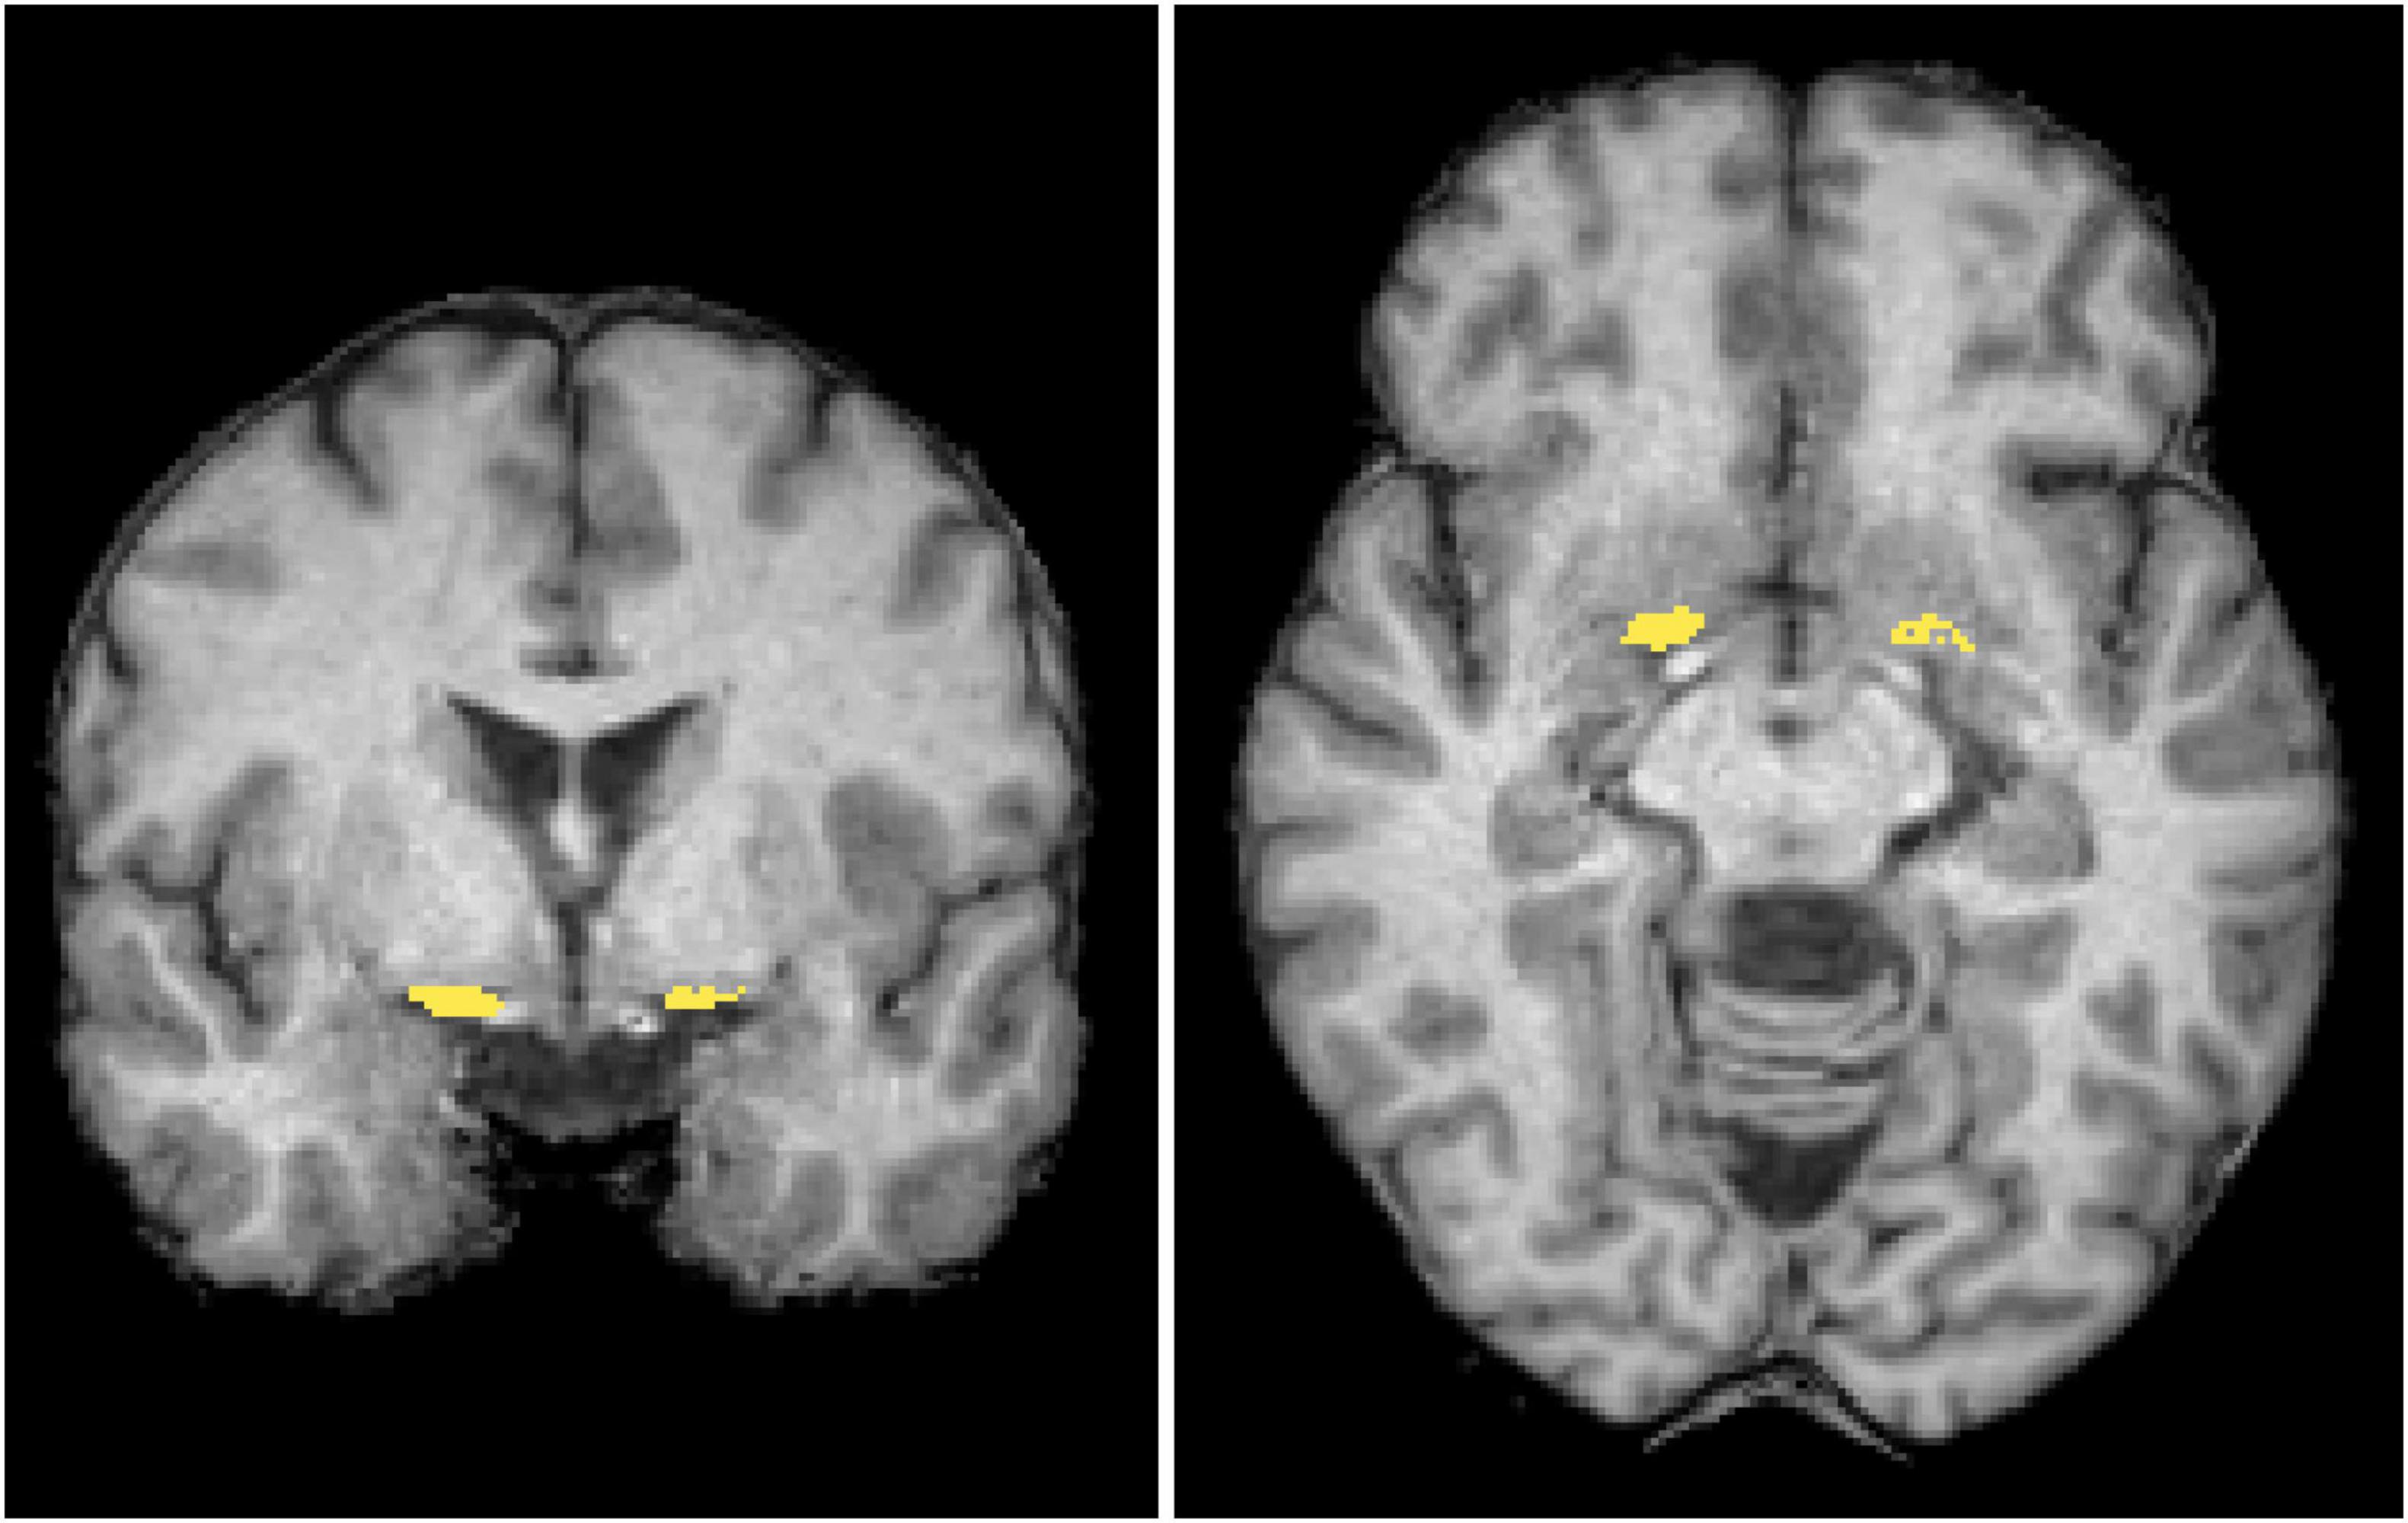

Morphometry analysis was conducted using SPM122 and CAT123. The 3D T1-weighted images were segmented into distinct tissue types and spatially normalized to the standard template through Diffeomorphic Anatomical Registration via Exponentiated Lie Algebra (DARTEL). The regions of interest (ROIs) of the NBM (Figure 2) were delineated based on the Julich-Brain Cytoarchitectonic Atlas (Amunts et al., 2020), which was developed using high-resolution imaging of histological sections from 23 postmortem human brains. To facilitate diffusion analysis, ROIs in the standard space were mapped back to each individual’s anatomical space by applying the inverse deformation field obtained from DARTEL. During spatial normalization, segmented maps were modulated by the Jacobian determinants of the deformation field to preserve local volumetric information. We then computed NBM volume by summing, within the ROI, the voxelwise product of the modulated segmentation and the NBM probability map.

FIGURE 2

Brain scan images showing two different views. The left image is a coronal view, and the right image is an axial view. Both images highlight specific brain regions with yellow markings, indicating areas of interest or activity. The brain’s structure is shown in varying shades of gray, emphasizing the highlighted areas.

Figure 2. Regions of interest. The mask of the nucleus basalis of Meynert (NBM) (yellow) is overlaid in coronal and axial views on a standard brain T1-weighted images in the MNI space. MNI, Montreal Neurological Institute.